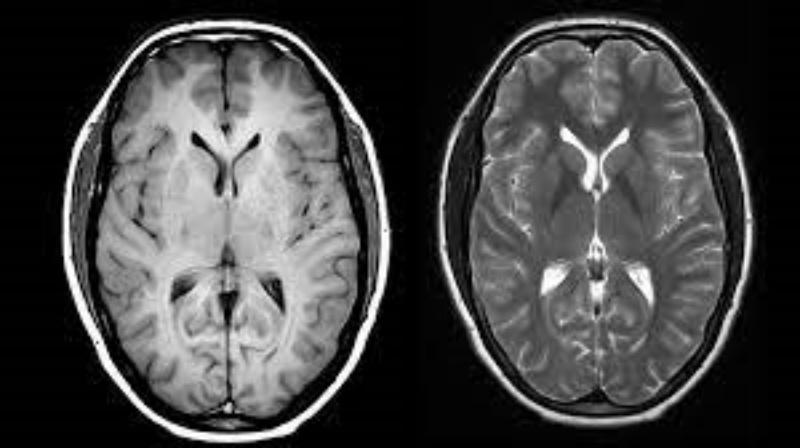

imagen de contraste,